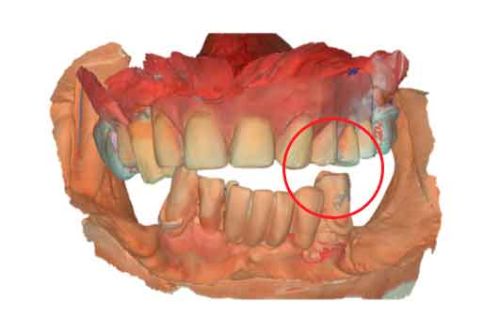

3D models - Bite scan from intra-oral scanner

Step 2 – CBCT acquisition

When traditional IOS scans lack necessary references, Cone Beam Computed Tomography (CBCT) data serves as a possible alternative. By utilizing CBCT scans, clinicians can establish accurate reference positions for treatment planning.

To be able to use CBCT data as initial models, we need to transform the DICOM file into an STL file.